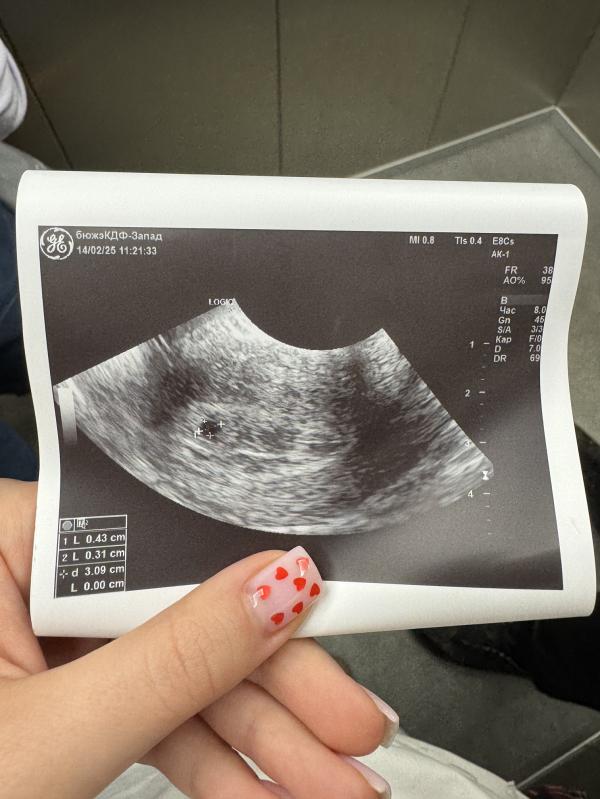

Первое УЗИ при задержке: что показывает, сроки по ПДМ и размеры плодного яйца на 6-7 день?

Моя крошка 🥹

Первое узи 🐣

6-7день задержки

Срок по пдм 5.3, по размерам плодного яйца 4.4

14.02.2025